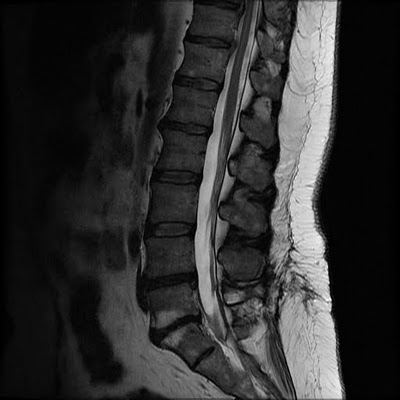

Epidural abscesses are inflammations near the site of the

epidural injection and are often undetectable since they are far below the surface

of the skin. Patients often can’t distinguish pain caused by the abscess from

the pain caused by meningitis. These abscesses can cause severe pain and

limited mobility and they must be drained. Dead tissue must be removed

surgically and months of anti-fungal medications must be administered in order

to clear the infection.

Arachnoiditis is a serious, chronic neurological condition

caused by trauma or infection of the arachnoid, a membrane surrounding the

spinal column. Patients with arachnoiditis are often in constant pain and

unable to stand or sit for long periods of time, in some cases even

experiencing incontinence. There is no cure for arachnoiditis; patients must

undergo consistent pain management therapy and treatment.